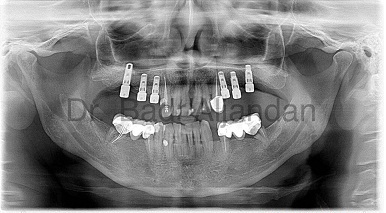

After the implant has bonded to the jawbone, the second phase begins. Dr. Al-jandan will uncover the implants and attach small posts that protrude through the gums and will act as anchors for the artificial teeth. When the artificial teeth are placed, these posts will not be seen. The entire procedure usually takes six to eight months. Most patients experience minimal disruption in their daily life.

Dental Implant placement is a team effort between an oral and maxillofacial surgeon and a restorative dentist. While Dr. Al-jandan performs the actual implant surgery, initial tooth extractions, and bone grafting if necessary, the restorative dentist (your dentist) fits and makes the permanent prosthesis. Your dentist will also make any temporary prosthesis needed during the implant process.

A single prosthesis (crown) is used to replace one missing tooth – each prosthetic tooth attaches to its own implant. A partial prosthesis (fixed bridge) can replace two or more teeth and may require only two or three implants. A complete dental prosthesis (fixed bridge) replaces all the teeth in your upper or lower jaw. The number of implants varies depending upon which type of complete prosthesis (removable or fixed) is recommended. A removable prosthesis (over denture) attaches to a bar or ball in socket attachments, whereas a fixed prosthesis is permanent and removable only by the dentist.